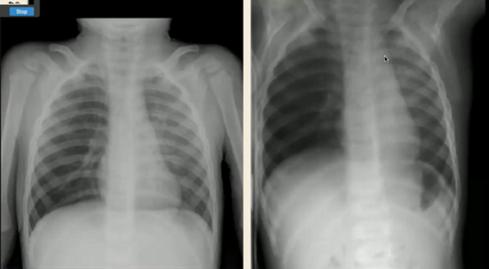

图6.新生儿暂时性呼吸增快症(左:生后胸片;右:生后20小时胸片)